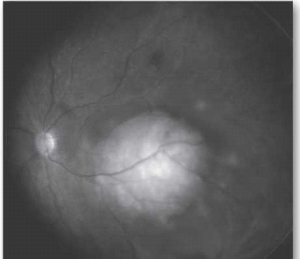

טיפול תוך-ורידי בכימותרפיה - IVC) Intravenous Chemotherapy)

טיפול תוך ורידי בכימותרפיה כולל בדרך כלל מתן של שלוש תרופות, Etoposide, Carboplatin ו-Vincristine, בשישה מחזורים בהפרש של כשלושה-ארבעה שבועות, עם טיפול מקומי עוקב בהרדמה מיד לאחר כל מחזור טיפולי. פרוטוקול זה נמצא יעיל כקו טיפול ראשון לשליטה על המחלה התוך עינית (תמונה 7), למניעת התפתחות גרורות, להורדת השכיחות של מעורבות בלוטת האצטרובל ולמניעת התפתחות גידולים משניים לאורך חיי החולה[45]. מכיוון שמתן הכימותרפיה לווריד מלווה תמיד בטיפול מקומי, צורת טיפול זאת קרויה כמורדוקציה (CRD, Chemoreduction). תופעות הלוואי העיקריות של הטיפול הן דיכוי חולף של מח העצם, רעילות כלייתית, סכנה לזיהומים ורעילות למערכת השמע של Carboplatin.